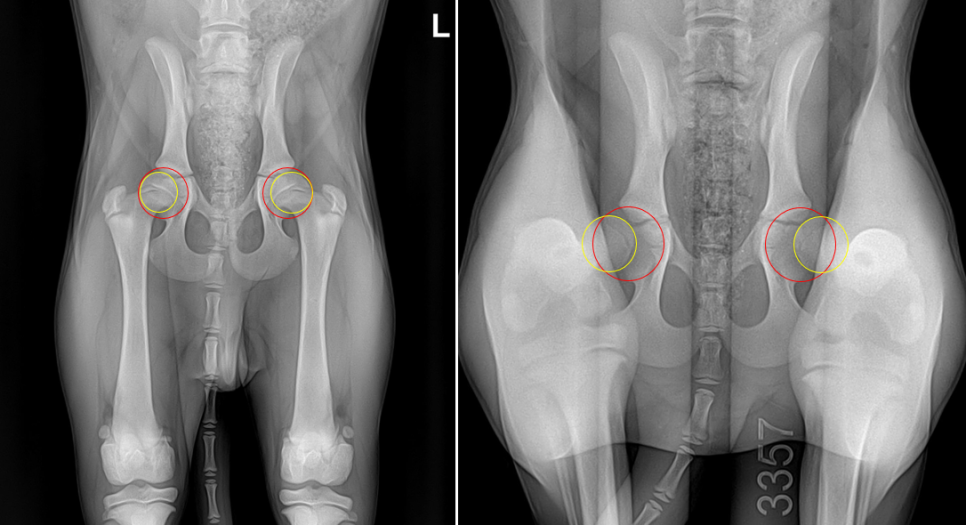

위 사진은 4개월령 루키의 같은날 촬영한 방사선 영상입니다.

골두가 들어가는 골반의 관골구에 빨간색의 가상의 원을 그리고 허벅지뼈의 골두에 가상의 원을 그린 후 노란색원이 빨간색원에서얼마나 빠져있는지 평가를 합니다. 같은 아이의 방사선 영상인데도 두 영상의 차이가 극명하게 드러납니다.

펜힙(Penn HIP)검사를 진행하지 않았다면 루키는 고관절 고위험군인지 인지하지 못하고 치료시기를 놓쳐 성견이 된 후 양측 고관절의 퇴행성 관절염이 발생했을 가능성이 매우 높습니다.

✔ 30%가 밀려나면 0.3, ✔ 60%가 밀려나면 0.6으로 표기하며 이를 DI (Distraction Index)라 합니다. DI는 0에서 0.0에서 1.0까지 측정 가능하며 수치가 낮을수록 선천적인 위험도가 낮아집니다. 평균적으로 0.3이하를 정상, 0.3~0.5사이를 경미한 위험군, 0.5~0.7사이를 중등도의 위험군, 0.7이상을 고위험군으로 분류합니다.

루키는 우측 0.61 좌측 0.62로 진단되어 중등도의 위험군으로 분류되어 추후 고관절 퇴행성 관절염 예방을 위한 JPS수술과 함께 중성화도 같이 진행하기로 결정하였습니다.